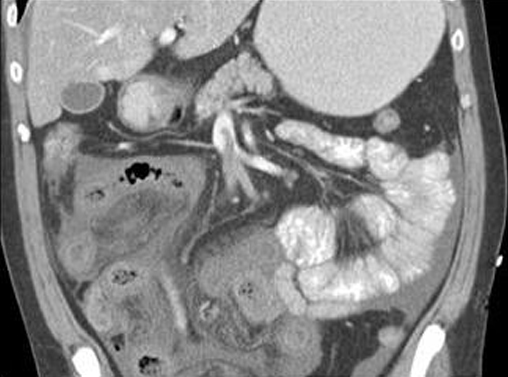

Colite pseudomembraneuse :

Epaisissement de la paroie et des haustrals du colon

ascendant et descendant se forment en aspect

empreinte de pouce au bord du colon . Image

radiologique TDM en coupe coronale |

|

Epaisissement de la paroi du

colon descendant avec aspect en scie de la muqueuse

du colon . Image radiologique TDM du colon en coupe

coronale . |